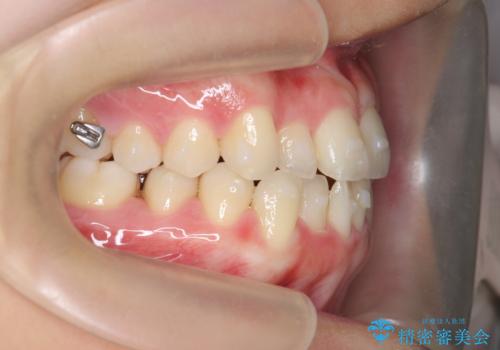

ガタつきの改善 マウスピース矯正治療

- 矯正装置

- インビザライン

- 歯のがたつきの改善を求めて、矯正治療を希望され来院されました。

少量の歯のディスキング、歯列弓拡大、アタッチメントを装着することで審美的な歯列へとマウスピース矯正インビザラインを用いて治療を行います。

マウスピース矯正は装着時間の遵守が非常に大切ですが、しっかりと20時間/日以上の装着を守っていただいたおかげで良好な治療結果を得ることができました。